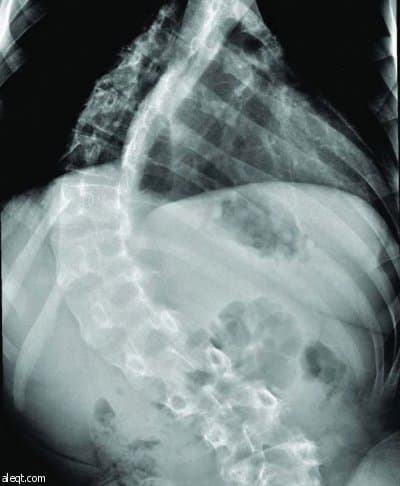

نجح فريق طبي في مستشفى الملك خالد الجامعي في جامعة الملك سعود في إنهاء معاناة مريض في الثالثة عشرة من عمره أصيب بالشلل نتيجة انحراف شديد في العمود الفقري (الجنف) وتأخر في العلاج حتى وصلت نسبة الانحناء إلى (140درجة).

وتم تنويم المريض بشكل عاجل وأجريت له عملية جراحية لإزالة الضغط عن الحبل الشوكي وتم تقويم الظهر من الخلف حيث تمكن المريض من المشي والعودة لممارسة حياته الطبيعية بعد العملية مباشرة ولله الحمد.

بدوره، ذكر الدكتور عبد المنعم الصديقي الأستاذ المساعد في كلية الطب واستشاري جراحة العظام والعمود الفقري في مستشفى الملك خالد الجامعي ورئيس الفريق الطبي لوحدة الجراحات التقويمية للعمود الفقري (الجنف)، أن الانحرافات في العمود الفقري تعد من الأمراض الخطيرة والمعقدة في أي المجتمع.

ونظراً لندرة المراكز الطبية و ندرة المتخصصين في هذا المجال ،الأمر الذي أدى إلى تأخر عديد من المرضى في تلقي العلاج و إيجاد صعوبات كثيرة في تعديل وتقويم هذه الانحرافات حيث تزداد نسبة الانحراف كلما تقدم بالمريض العمر وتأخر العلاج.